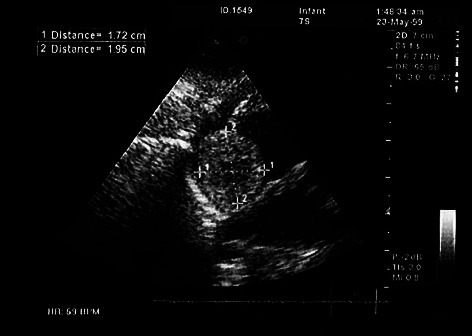

Introduction: Different subtypes of cardiac tumors containing spindle cells have been described as cardiac sarcoma. However, benign types have not been reported so far. We described a neonate with progressive respiratory distress who had a PDA and was finally diagnosed with a right atrial spindle cell tumor. Case Presentation: The patient was a neonate referred with respiratory distress and sepsis. The initial echocardiography demonstrated a small atrial septal defect, patent ductus arteriosus, and a heterogeneous rounded right atrial mass lesion. Pathologic examination confirmed the right atrial myxoid spindle cell tumor without local invasion. Successful mass resection was performed, and follow-up echocardiography revealed normal cardiac structure and function. Conclusion: In infants with manifestations of possible cardiac anomalies, it is necessary to consider other pathologies, such as neoplastic processes. Spindle cell detection in pathology is not ominous all the time, and there are benign subtypes with favorable outcomes after successful surgical resection.